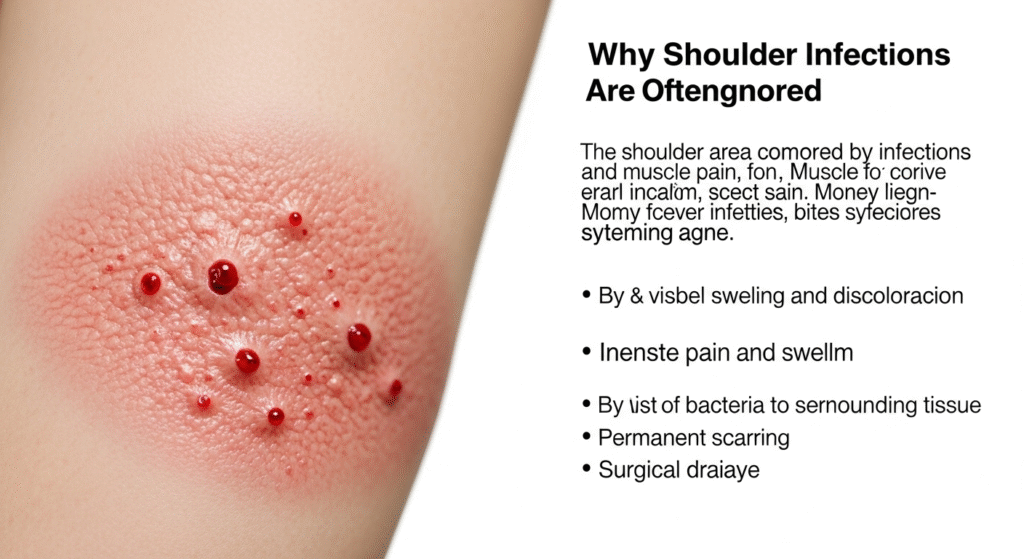

⚠️ Why Shoulder Infections Are Often Ignored

The shoulder area is commonly covered by clothing, which allows infections to worsen unnoticed. Many people mistake early symptoms for muscle pain, insect bites, or acne.

By the time visible swelling and discoloration appear, the infection may already be advanced.

Ignoring such signs can lead to:

- Intense pain and swelling

- Spread of bacteria to surrounding tissue

- Permanent scarring

- Surgical drainage

- Risk of systemic infection in rare cases